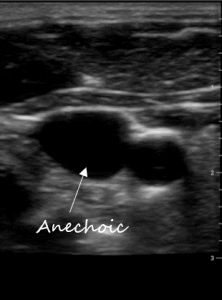

Communication works best when were are all using the same language. Describing ultrasound images is no different. All ultrasound terms are based on describing how sound is reflected. Below are terms used to describe the appearance of body structures on ultrasound:

Gain: this can be thought of as the ‘brightness’. The higher the gain the whiter things get; the lower the gain the darker things get. Gain is a processing function and doesn’t change any of the characteristics of the ultrasound beam itself. Optimal gain is achieved when anechoic structures like fluid or blood are black and hypoechoic tissue like subcutaneous tissue or organs are grey and hyperechoic structures like arterial walls, pleura, and bone are white.